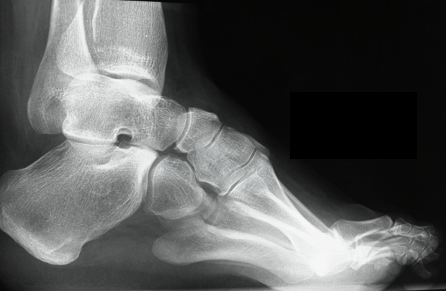

X-ray

Meary's angle

- longitudinal talus axis - 1st metatarsal angle

- normal 0o

- cavus > 20o

Calcaneal Pitch

- normal 20o or less

- > 30o abnormal